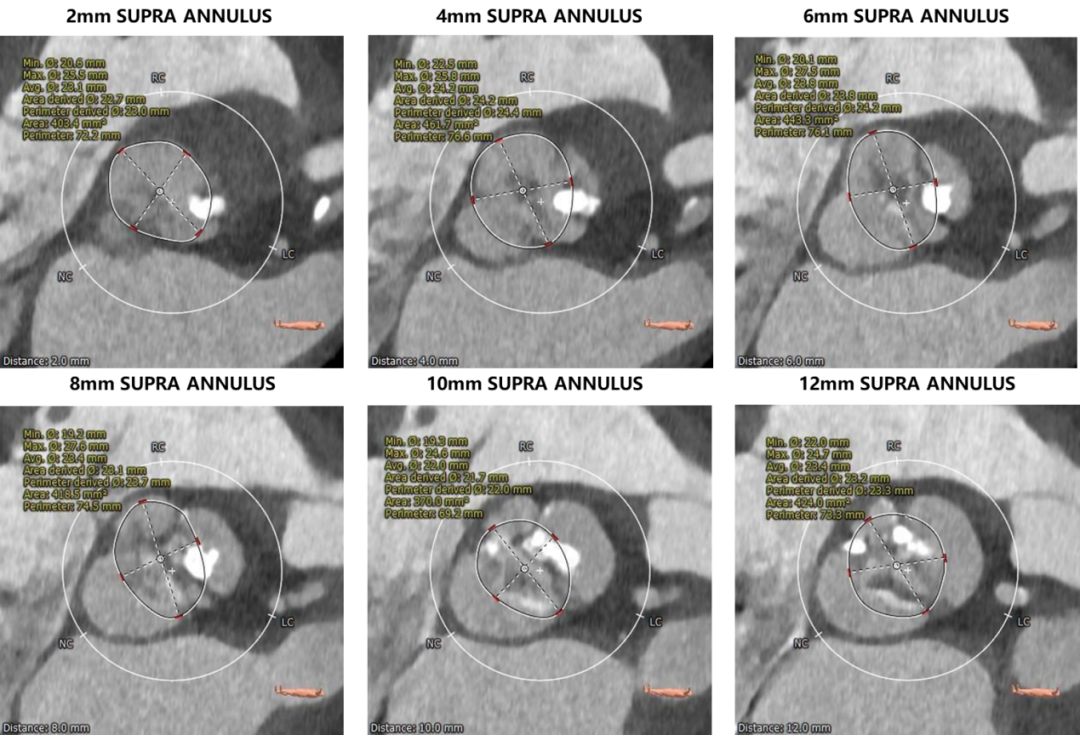

瓣环上解剖结构评估:

3.根据CT测量瓣环及瓣上结构数值,推荐选择22mm球囊预扩张,AV26瓣膜。